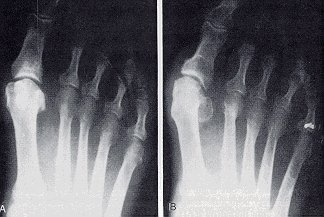

Figure 5

The Reverdin-Isham procedure.

- A dorsoplantar view demonstrating the portion of the medial eminence resected and the level at which the osteotomy is performed.

- The same view showing the wedge of bone resected to achieve correction.

- The correction is made with the arrow showing the direction of closure.

- A medial view of the first metatarsal demonstrating the plantar-medial incision, the capsulotomy, and the placement of the bone cutting instrument prior to the osteotomy.

- After the removal of the wedge and before closure.

- The completed osteotomy after closure and correction of the structural deformity.